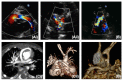

Hypoplastic left heart syndrome (HLHS) is a spectrum of left heart underdevelopment leaving the left side unable to support the systemic circulation. If active management is pursued, then the condition is managed with staged palliation to the Fontan circulation, leaving a systemic right ventricle. Through all surgical stages, and even after completion of Fontan, there are multiple areas that may require intervention, most frequently the branch pulmonary arteries which are essential to a successful Fontan circulation. Echocardiography is the mainstay of assessment, but there is an increasing use of magnetic resonance imaging (MRI) and computed tomography (CT) particularly in relation to extracardiac structures which can be more challenging with echocardiography. Both MRI and CT require set-up, experience and training, and usually sedation or anesthetic in smaller children, but can provide excellent imaging to guide interventions. Cardiac MRI is also able to quantify right ventricular (RV) function which can be challenging on echocardiography. This article describes the modalities available and their use in assessing patients with HLHS prior to catheter interventions.